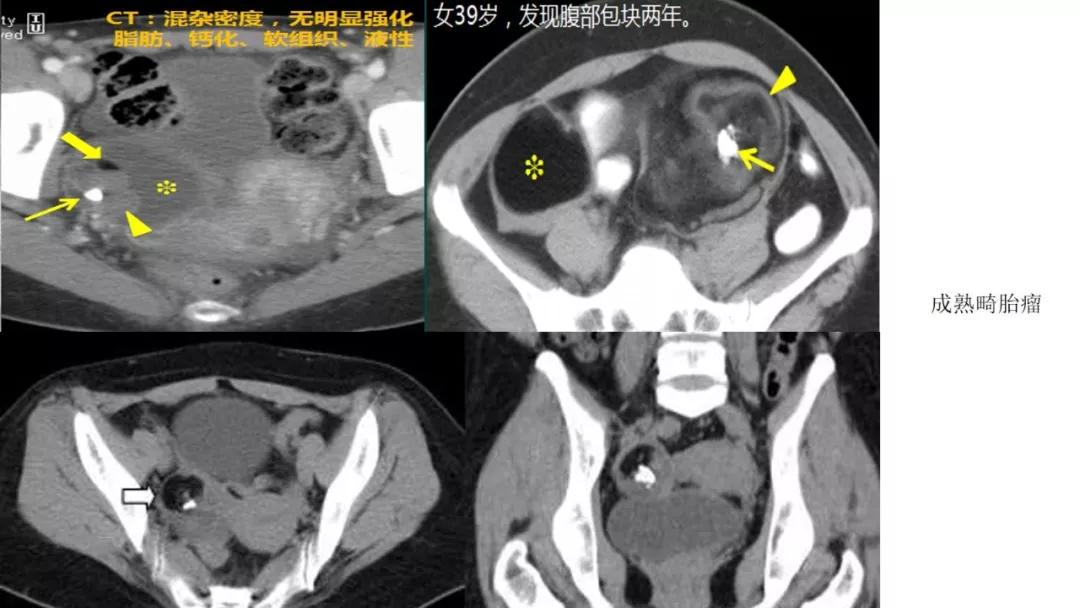

生殖细胞肿瘤占卵巢肿瘤的20%,以成熟畸胎瘤-皮样囊肿多见,良性多,恶性少。表现为囊实性混合性或实性肿块,大多数含有脂肪、钙化等特征。

良性者常呈囊性肿块,脂囊,脂液囊,液囊。少数混合成分,实性。壁光整可稍厚,囊内有脂、液分层现象,多数伴有粗大钙化或骨骼。

恶性者常呈实性或混杂性肿块,多数边界清楚,可伴有不规则沙粒状钙化。无性细胞瘤常为实性肿块,轻度强化,内胚窦瘤实性成分明显强化,不成熟畸胎瘤呈混杂密度。结合年龄及临床生化检查,有助于诊断。

出现脂肪:畸胎瘤,囊性为主是成熟、实性为主是不成熟

出现钙化:浆液性肿瘤、卵泡膜纤维瘤、畸胎瘤、Brenner瘤

女,39 岁,体检发现盆腔肿块1月余

CA125:51U/ml